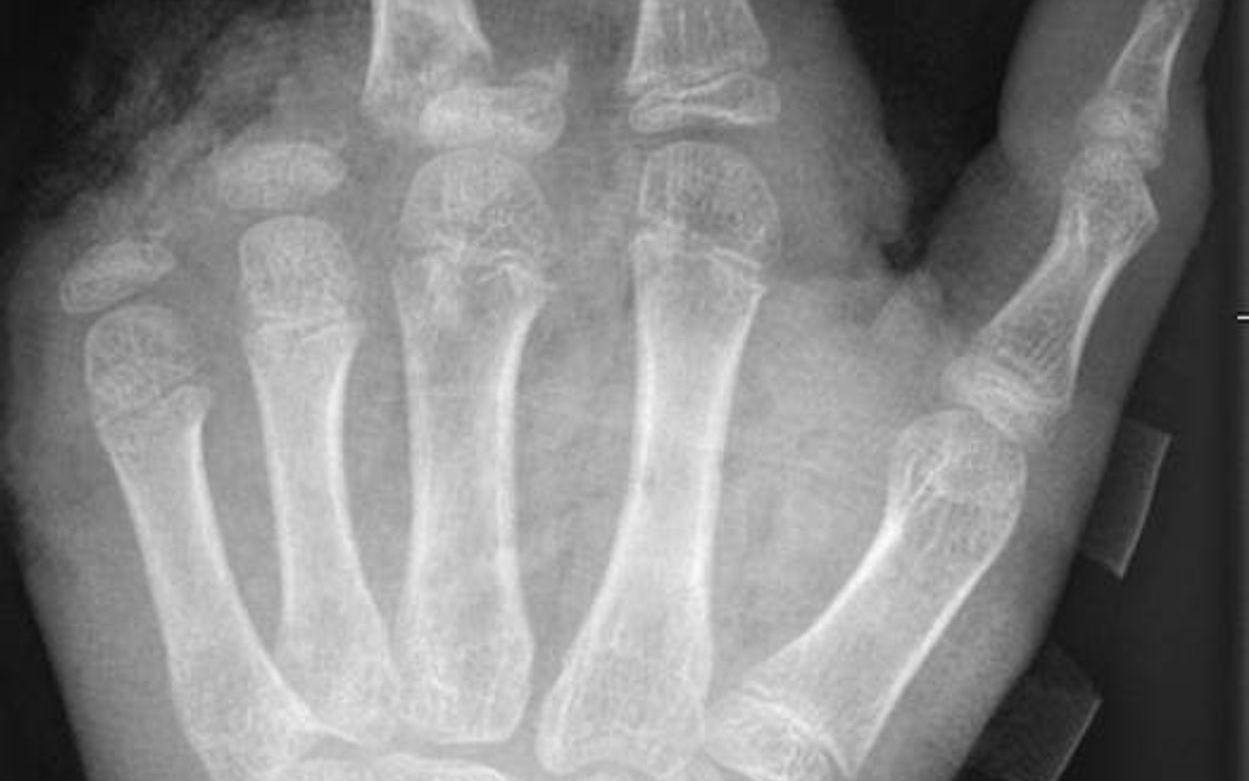

Berlin (dpa) - Abgetrennte Finger, durchtrennte Sehnen, Amputationen - die Handchirurgin Leila Harhaus-Wähner hat in der Silvesternacht schon vieles gesehen. Auch in diesem Jahr rechnet die Berliner Ärztin mit zahlreichen Böller-Verletzten. «Für Handchirurgen ist es klar, dass Silvester die arbeitsreichste Nacht sein kann.» Bis 24 Uhr passiere erstmal nicht so viel, ab 1 Uhr, 2 Uhr nachts kämen immer mehr Verletzte in die Notaufnahme und dann «sehr viele in sehr kurzer Zeit.»

In der Handchirurgie müssten an Silvester im Unfallkrankenhaus rund 20 bis 40 Menschen mit Böllerverletzungen operiert werden, sagt die Ärztin. Dieses Jahr werde sie mir vier weiteren Handchirurgen im Einsatz sein. Die häufigsten Verletzungen entstünden durch explodierende Böller in der Hand.

«Der überwiegende Teil der Verletzungen trägt tatsächlich lebenslange Folgen mit sich, weil die Sprengkraft dazu führt, dass eben nicht nur einzelne Strukturen verletzt sind, sondern immer mehrere. Und das heilt praktisch nie ganz folgenlos ab.» Zum Teil könnten Hände nicht mehr gerettet und müssten amputiert werden.